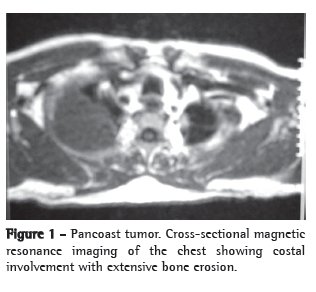

We report a case of a 74-year-old hypertensive white male, a painter, with peripheral vascular insufficiency of the lower limbs. The patient had been a smoker for 54 years (one pack of cigarettes per day). He presented with a two-month history of sharp, right-sided pleuritic pain, accompanied by productive cough with watery expectoration, as well as by dyspnea upon exertion. Physical examination at admission showed only universal reduction in breath sounds, and reduced dorsalis pedis pulse rate, without neurological deficits. No alterations were observed in the results of the blood workup, biochemical blood tests or urinalysis. His PPD was nonreactor and testing for acid-fast bacilli in sputum was negative. Chest imaging tests (Figures 1 and 2) showed a mass with regular borders in the right superior sulcus, affecting the adjacent vertebrae and ribs. Whole-body gallium scintigraphy and CT of the skull were normal. The patient was submitted to thoracic punch biopsy, the histopathological study of which showed small cell lung carcinoma (Figure 3). During his hospital stay, the patient evolved to paresthesia in the right axilla region and worsening of the chest pain, which became intense over the right scapula.

The pulmonary mass was investigated using CT and magnetic resonance imaging of the chest. Even with the advances in CT imaging acquisition techniques, with better detection and evaluation of the tumor growth, as well as of the extent of infiltration into the chest wall and mediastinal involvement,(9) magnetic resonance imaging of the chest is still the best means of evaluating superior sulcus tumors.(10-12) Although magnetic resonance imaging of the chest provides the same information that CT does, it allows better evaluation of the central nervous system impairment.(10)